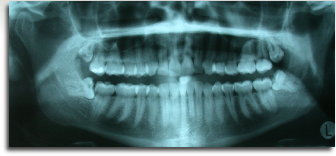

The wisdom tooth (or third molar) is usually the last tooth to erupt into the mouth anytime after about 16 years of age. Frequently there is not enough room to accommodate wisdom teeth and as such they do not come into the mouth normally. When this happens, the wisdom teeth are said to be “impacted”.